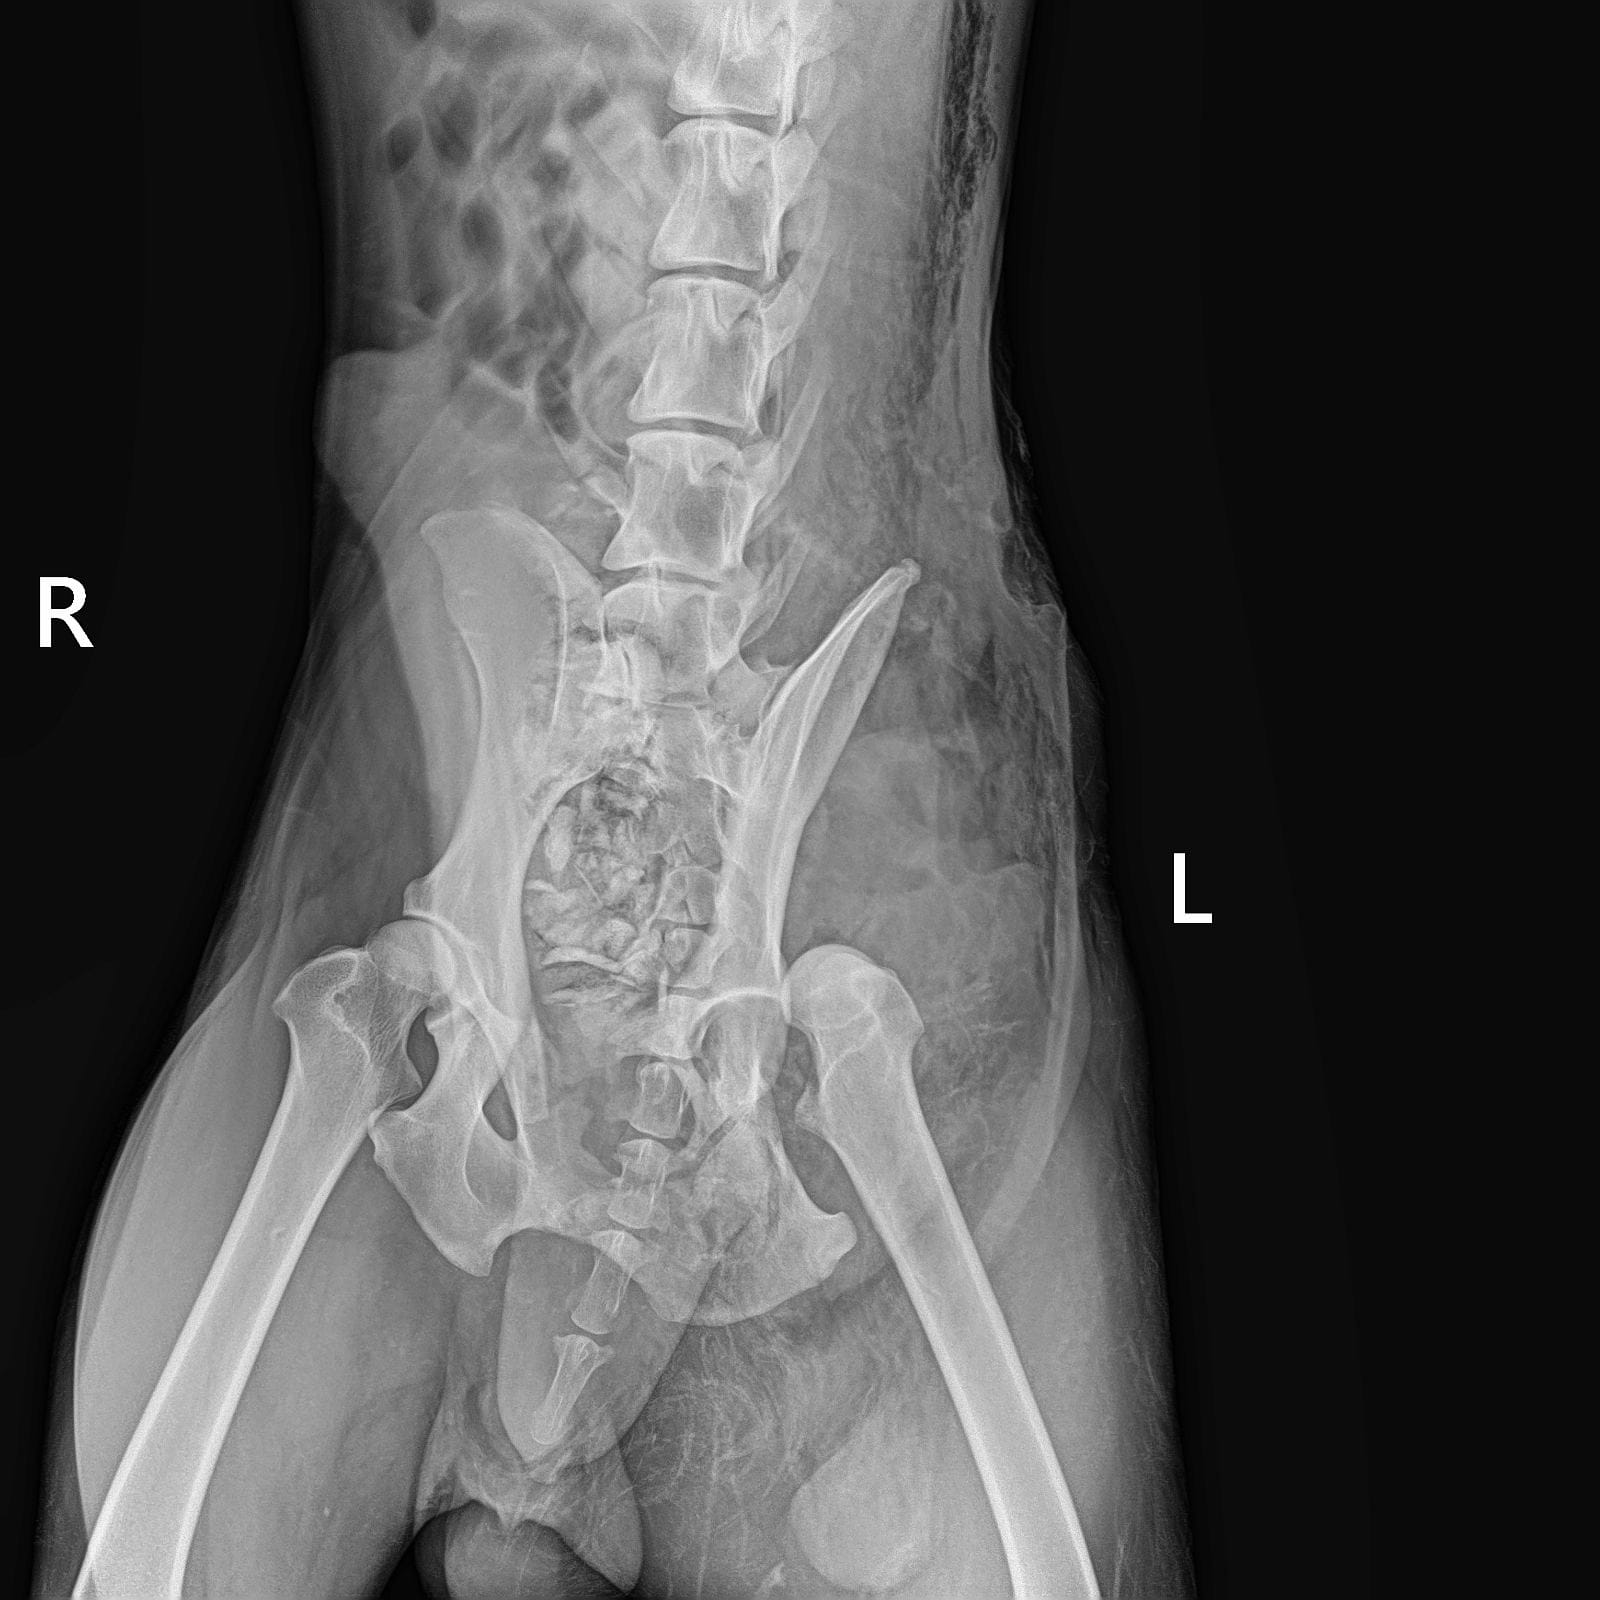

Обследования из клиники Рекс